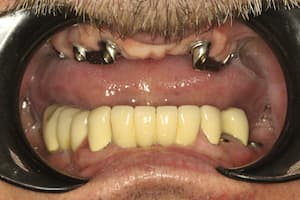

Альтернативный вариант несъемного протезирования. Полная адентия (отсутствие) зубов на верхней челюсти. Применения технологии all on 6. Имплантация 6 зубов системой Neodent на верхней челюсти. Протезирование зубов коронками Telio Cad армированными титановой балкой.

До

После

Удаление семи зубов на верхней челюсти. Одномоментная имплантация системой Neodent 6 зубов, предназначенная для немедленной нагрузки (изготовление временных коронок в день имплантации). В день имплантации сняли оттиски для временного протезирования Telio Cad. Конструкция была установлена через 2 недели после имплантации.